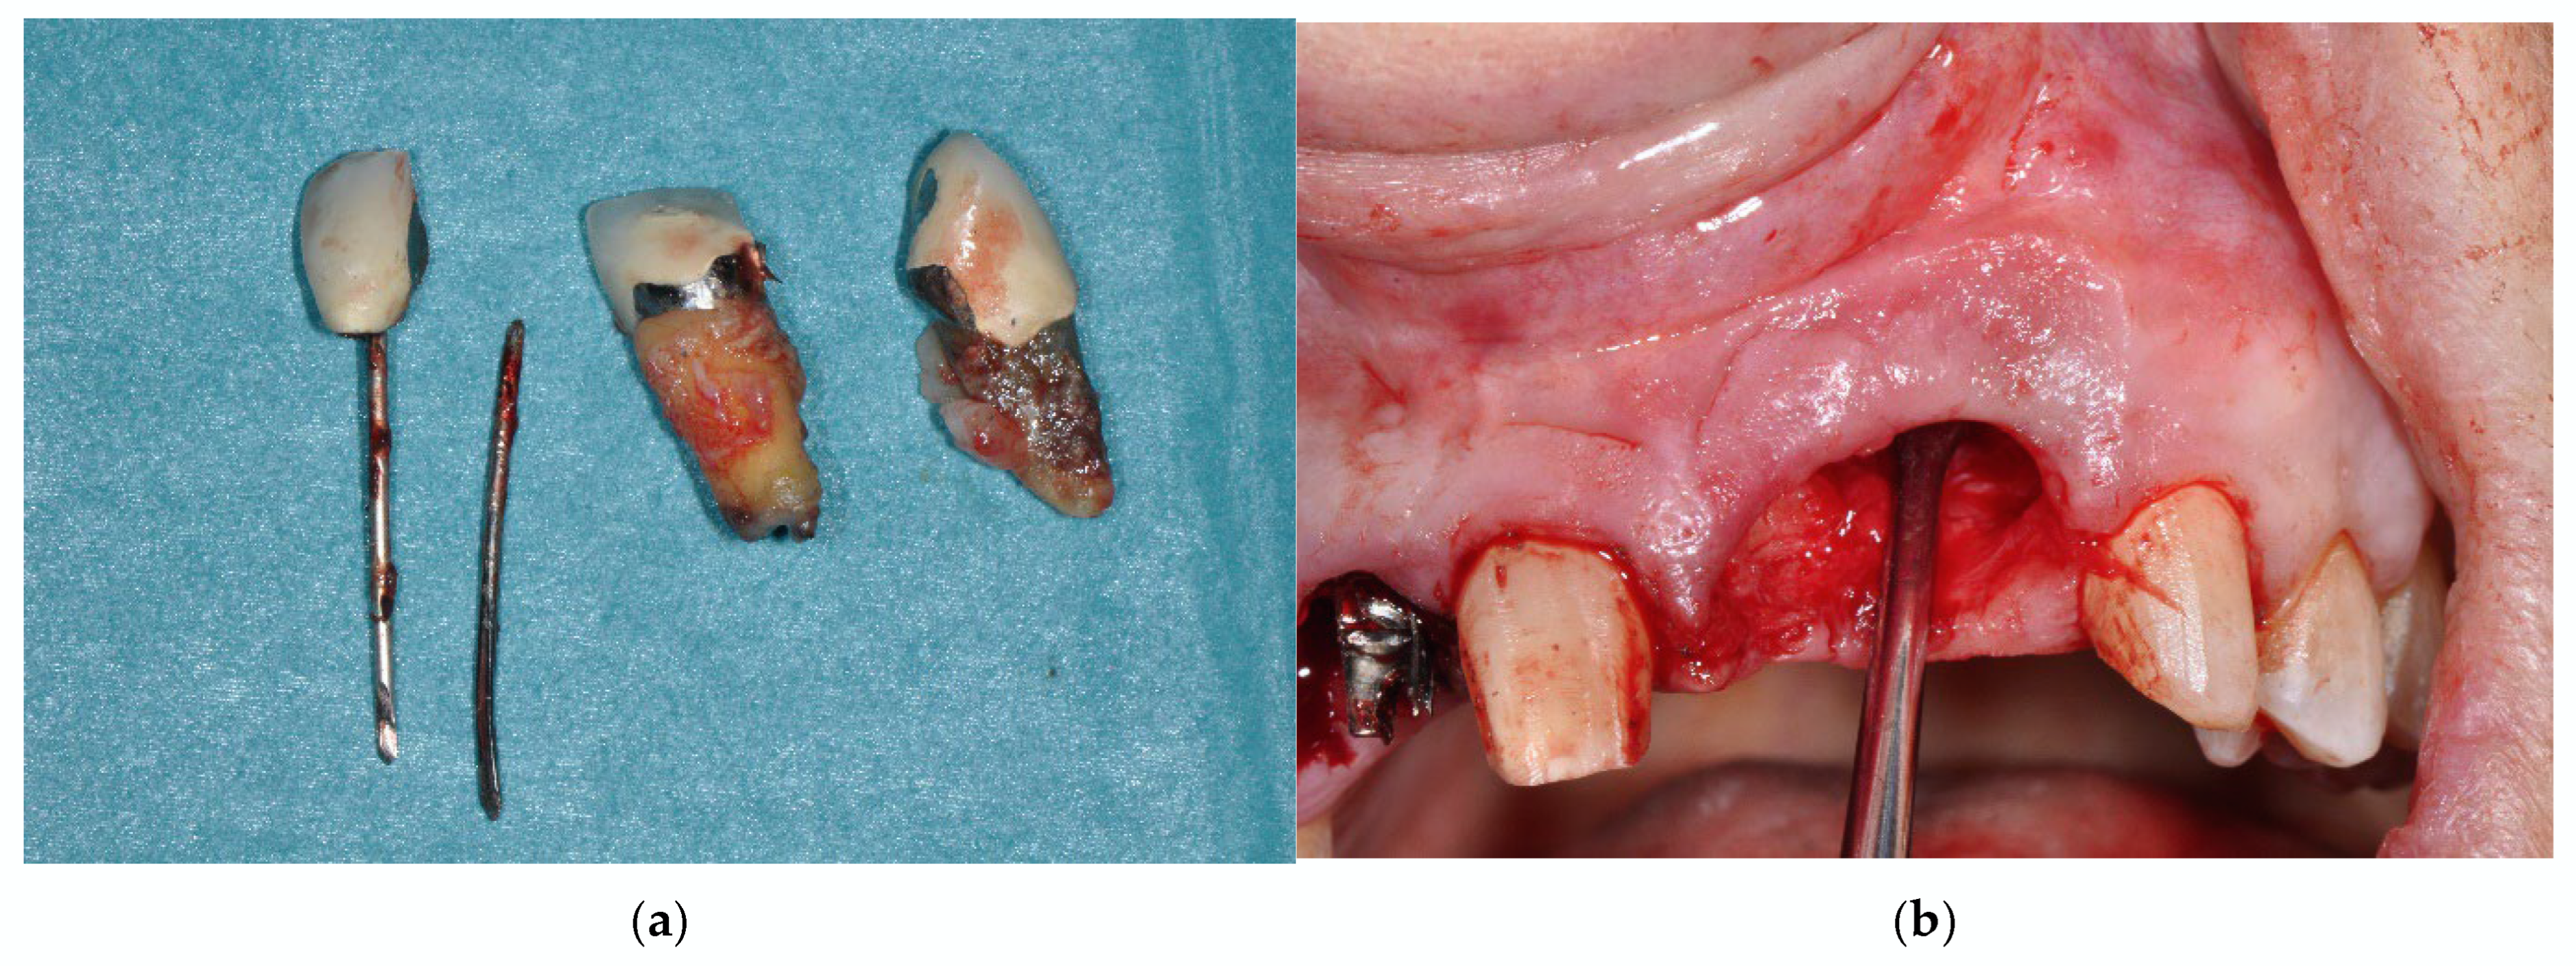

2.2. Surgical Procedure